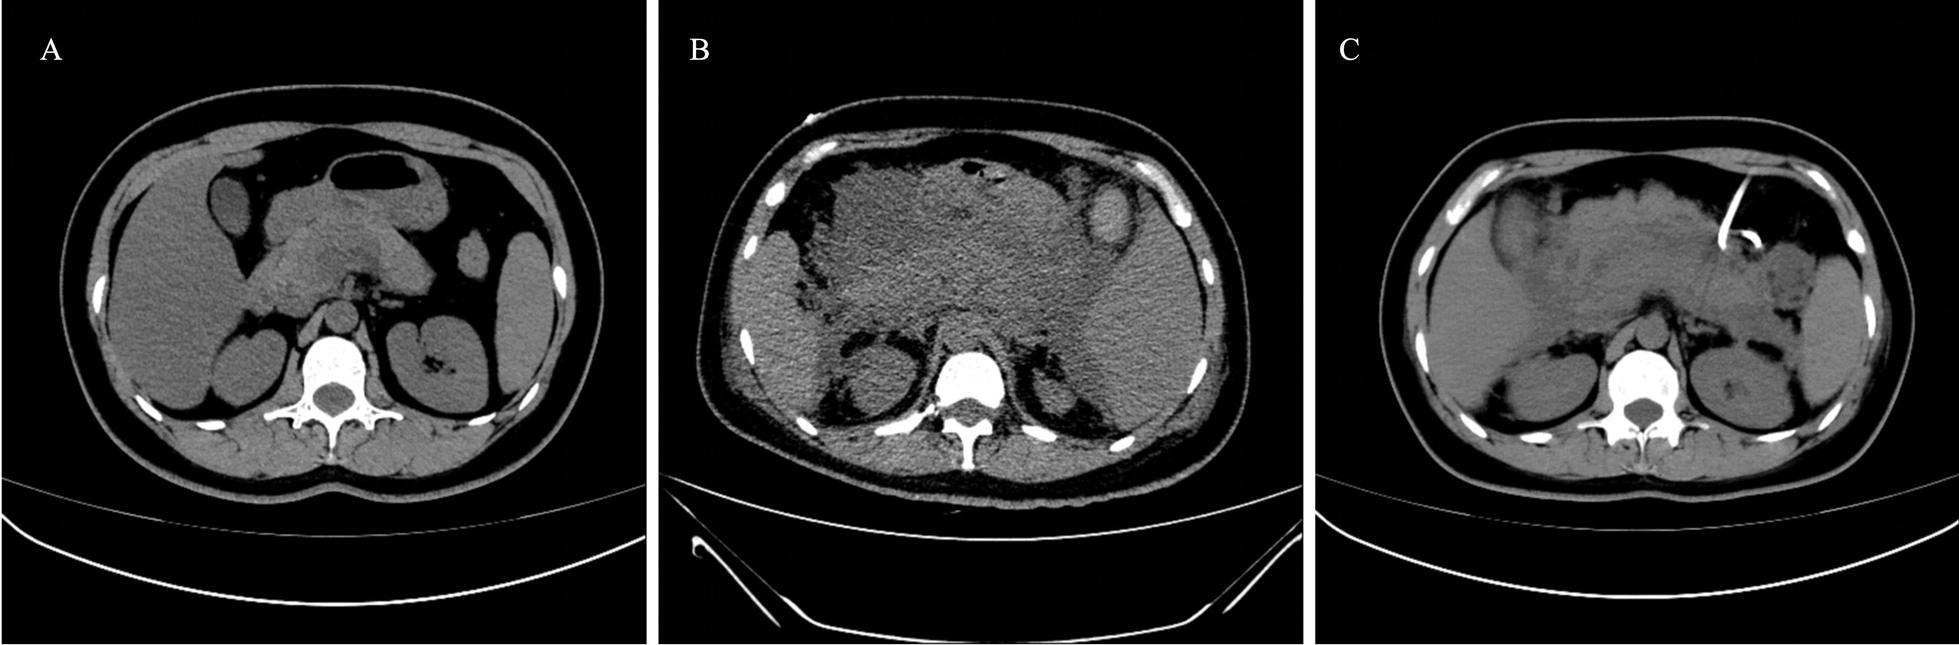

Whether there is a direct causal relationship between pancreatitis and posterior reversible encephalopathy syndrome needs further study. We here report a 39-year-old Chinese woman who was diagnosed with pancreatitis followed by vision disturbance. The patient was finally diagnosed with posterior reversible encephalopathy syndrome. On the basis of this rare case, we analyzed the causes of visual disturbance and proposed diagnostic ideas.

胰腺炎与后部可逆性脑病综合征之间是否存在直接因果关系尚需进一步研究。我们在此报告一例 39 岁的中国女性,该患者被诊断为胰腺炎后出现视力障碍。最终该患者被诊断为后部可逆性脑病综合征。基于这一罕见病例,我们分析了视力障碍的病因并提出了诊断思路。